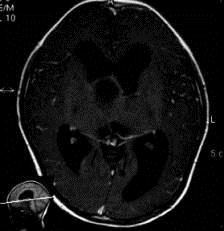

问题 病历摘要:??患者女性,6岁,半年来感觉视力模糊,近10天出现反复头痛,间有恶心呕吐,精神转差,查体:神志清楚,身高90cm,体重25Kg,血压90/55mmHg,右眼视力4.6,左眼视力4.8,双侧视乳头水肿,颈软,伸舌居中,四肢肌张力正常,肌力5级,双侧Babinski征(-)。 患者术后第一天,神志嗜睡,精神疲倦,皮肤干燥,38.2℃,心率155次/分,Bp102/60mmHg,中心静脉压3mmHO,Na160mmol/L,尿量很多,色清如水,应作的处理措施有?